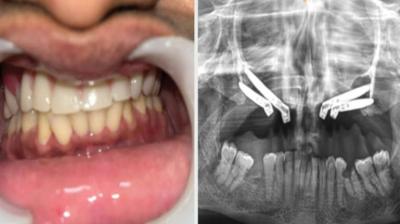

एम्स भोपाल में जटिल सर्जरी सफल, युवती को मिला नया जीवन

एम्म में जटिल सर्जरी को सफलतापूर्वक अंजाम दिया है। इस सर्जरी में ट्यूमर के कारण काटे गए निचले जबड़े को पैर की हड्डी से दोबारा बनाया गया और उसमें 13...